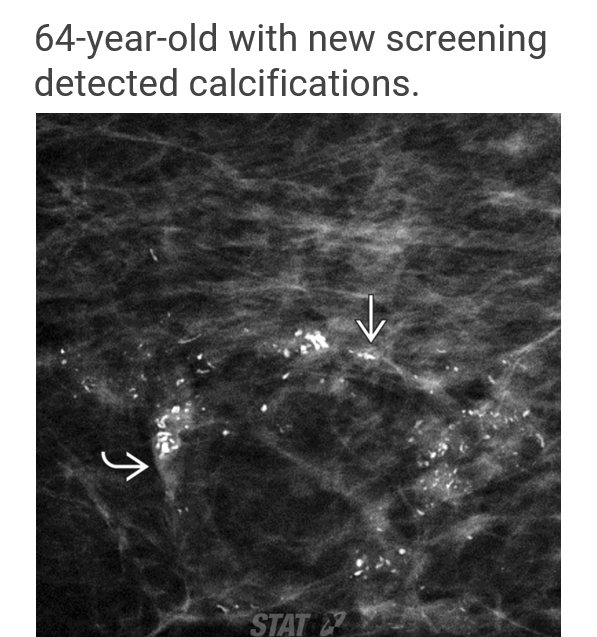

most common distribution of calcs in DCIS

**grouped!!

Calc distribution most suggestive of DCIS

linear or segmental

(most specific for DCIS, but not the most common presentation)